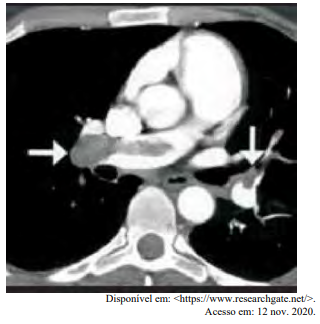

Certa idosa de 70 anos de idade é levada ao consultório médico por familiares, com relato de dor no peito há oito horas. Quanto a comorbidades, ela apresenta hipertensão arterial sistêmica e insuficiência cardíaca. Estava em casa assistindo à televisão quando sentiu uma dor súbita no peito, de moderada intensidade, que piora com a inspiração profunda, irradiando para o dorso, em queimação e associada a palpitações e a falta de ar importante, mesmo em repouso. Nega náuseas e sudorese. Não melhora após tomar dipirona. A dor continua da mesma forma, mas o que levou os familiares a procurarem atendimento foi a piora da falta de ar. Faz uso de losartana, atenolol, espironolactona, AAS e sinvastatina. Nega etilismo e informa que tinha o hábito de tabagismo, mas parou há mais de 10 anos. Tem histórico anterior de cirurgia de artroplastia de quadril há mais de um ano. Tem ficado muito tempo em repouso, assistindo à TV, principalmente depois da pandemia de Covid-19. Ao exame físico, constatam-se PA = 89 mmHg x 59 mmHg, FC = 125 bpm, FR = 27 ipm e SatO2 = 89% em ar ambiente. A paciente está afebril, em estado geral regular, lúcida, orientada e comunicativa. As auscultas pulmonar e cardíaca mostram-se sem alterações. Observam-se abdome inocente, membros inferiores com cacifo + discreto e simétrico, panturrilhas livres e pulsos preservados. A paciente realiza o eletrocardiograma e a tomografia de tórax, conforme representado nas imagens a seguir.

Com base nesse caso clínico, nos exames representados nas imagens e nos conhecimentos médicos correlatos, julgue o item a seguir.

Sabe-se que a maioria dos êmbolos pulmonares têm origem nos membros inferiores. Ao examinar a paciente, não foi observado empastamento nos membros inferiores. Pode-se, então, concluir que a hipótese diagnóstica de TEP seja pouco provável.